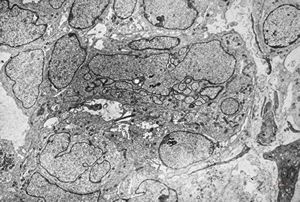

M,55y. | meningotheliomatous meningeoma

F,75y. | meningotheliomatous meningeoma